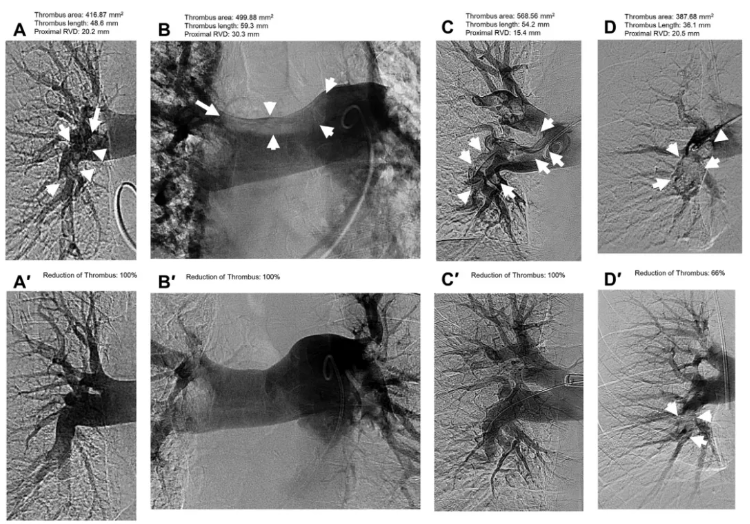

SCAI:治療急性肺栓塞神器Hēlo取栓系統(tǒng)首揭神秘面紗——新型取栓系統(tǒng)在治療急性肺栓塞中具有良好的安全性和可行性來(lái)自ENGULF試驗(yàn)的最新數(shù)據(jù)表明,一種新型雙作用取栓裝置在治療急性肺栓塞(PE)方面是有效和安全的。安全性和有效性的結(jié)果5月7日?(當(dāng)?shù)貢r(shí)間)?在心血管血管造影與介入學(xué)會(huì)(SCAI)2024年科學(xué)會(huì)議上作為最新科學(xué)提出,并同時(shí)發(fā)表在JSCAI上。肺動(dòng)脈栓塞(PE)是一種嚴(yán)重的心血管疾病,血栓會(huì)導(dǎo)致肺部血液流動(dòng)和氧氣水平出現(xiàn)問(wèn)題。該病可能危及生命,多達(dá)30%的患者在確診后一個(gè)月內(nèi)死亡。盡管最近在治療選擇方面取得了進(jìn)展,PE仍然具有很高的死亡率和發(fā)病率,很少有米國(guó)食品和藥物管理局(FDA)批準(zhǔn)的血栓切除術(shù)導(dǎo)管可供醫(yī)生使用。ENGULF試驗(yàn)是一項(xiàng)前瞻性,單臂,首次人體,安全性和可行性研究,評(píng)估一種新型栓塞切除導(dǎo)管系統(tǒng),用于治療急性PE,該系統(tǒng)具有可操縱和可擴(kuò)展的漏斗和內(nèi)部攪拌器,Hēlo?PE取栓系統(tǒng)?;颊呓邮苄g(shù)前和術(shù)后48小時(shí)計(jì)算機(jī)斷層掃描(CT)。主要療效指標(biāo)是手術(shù)前后右心室與左心室(RV/LV)比值的百分比差異。主要和次要安全性指標(biāo)為全因死亡率、重大危及生命的出血、器械相關(guān)的嚴(yán)重不良事件、肺或心臟損傷以及術(shù)后48小時(shí)和30天的臨床失代償。(A)?Hēlo?PE取栓系統(tǒng)“開(kāi)放漏斗”結(jié)構(gòu)示意圖。(B)HeloPE一體化手柄示意圖獨(dú)特的漏斗設(shè)計(jì)自膨脹設(shè)計(jì)確保寬遠(yuǎn)端開(kāi)口,有效的大口徑血栓接合雙重作用的技術(shù)小輪廓系統(tǒng)打破并通過(guò)結(jié)合高速攪拌和同時(shí)醫(yī)生控制的抽吸去除血栓單通道導(dǎo)管設(shè)計(jì)和集成手柄,方便復(fù)雜解剖的導(dǎo)航來(lái)自8個(gè)中心的25例患者均成功切除了栓子。平均RV/LV比值基線時(shí)為1.53±0.27,術(shù)后48小時(shí)為1.15±0.18(變化23.2%±12.81%)。值得注意的是,48小時(shí)內(nèi)沒(méi)有發(fā)生重大不良事件,30天內(nèi)沒(méi)有死亡。賓夕法尼亞大學(xué)醫(yī)學(xué)臨床醫(yī)學(xué)助理教授、該研究的主要作者TaiKobayashi醫(yī)學(xué)博士指出:雖然需要更嚴(yán)格的研究,但RV/LV比率是急性PE功能障礙和不良后果的最重要預(yù)測(cè)指標(biāo),令人興奮的是,在新的首次人體裝置中,RV/LV比率的降低與市場(chǎng)上其他FDA批準(zhǔn)的設(shè)備一樣多,沒(méi)有任何大的安全性問(wèn)題。這項(xiàng)技術(shù)代表了大口徑和小口徑栓子切除術(shù)之間的結(jié)合,它允許操作員使用更小的導(dǎo)管穿過(guò)心臟,但擴(kuò)大更大的漏斗,以匹配大口徑導(dǎo)管的大小,留下更小的足跡,降低患者血液動(dòng)力學(xué)影響的風(fēng)險(xiǎn)。該研究的資深作者、國(guó)家首席研究員是賓夕法尼亞大學(xué)費(fèi)城醫(yī)院心血管導(dǎo)管實(shí)驗(yàn)室主任JayGiri醫(yī)學(xué)博士,Giri指出:為了使介入PE治療領(lǐng)域充分發(fā)揮其潛力,需要不斷創(chuàng)新,以?xún)?yōu)化我們?cè)谑苓@種疾病影響的廣泛患者中的手術(shù)工作流程。在這一過(guò)程中,ENGULF試驗(yàn)是重要的一步,它證明了一種新型的、專(zhuān)用的PE取栓導(dǎo)管即使在最早的用戶(hù)中也能取得優(yōu)異的效果。上述研究相關(guān)信息盡管肺栓塞(PE)的治療取得了進(jìn)展,但與該疾病相關(guān)的死亡率仍然很高特別是,基于生物標(biāo)志物升高的心臟成像右心室(RV)應(yīng)變和心肌損傷患者在30天內(nèi)仍然具有很高的死亡率。在過(guò)去的十年中,隨著微創(chuàng)導(dǎo)管裝置的引入,包括定向溶栓治療和機(jī)械取栓,在中度風(fēng)險(xiǎn)PE的管理方面有了顯著的創(chuàng)新。目前,米國(guó)只有兩種導(dǎo)管取栓系統(tǒng)獲得食品和藥物管理局的批準(zhǔn):?FlowTriver(InariMedical),一種16F-24F的吸吮式取栓系統(tǒng),以及LightningIndigo(PenumbraInc),一種8F-16F的連續(xù)式吸栓系統(tǒng)。使用大口徑FlowTriever裝置,曾有因右心室和右側(cè)心臟瓣膜力學(xué)破壞而導(dǎo)致血流動(dòng)力學(xué)不穩(wěn)定的病例報(bào)告。相反,僅依靠吸力的小口徑導(dǎo)管系統(tǒng)可能缺乏清除大量血栓的能力,并有嚴(yán)重失血的風(fēng)險(xiǎn)。HēloPE取栓系統(tǒng)(EndovascularEngineering,Inc)旨在解決目前可用的吸力取栓系統(tǒng)的局限性。HēloPE導(dǎo)管設(shè)計(jì)獨(dú)特,為16F輸送導(dǎo)管,結(jié)合可折疊的24F漏斗尖端,允許類(lèi)似于大口徑系統(tǒng)的血栓接合,但具有較小的裝置輪廓。該裝置具有雙關(guān)節(jié),便于在肺動(dòng)脈系統(tǒng)中導(dǎo)航。此外,漏斗內(nèi)的內(nèi)部攪拌器有助于血栓的機(jī)械破壞和攝入,特別是那些更纖維化和有組織的血栓,以增強(qiáng)而不僅僅依賴(lài)于連續(xù)的吸入特性。這項(xiàng)首次人體研究的目的是研究HēloPE取栓導(dǎo)管治療中危PE患者的安全性和可行性。這項(xiàng)前瞻性的首次人體研究證明了HēloPE取栓導(dǎo)管治療急性中危PE患者的安全性和可行性。HēloPE取栓導(dǎo)管安全,成功降低了RV/LV比值(-0.38,23.4%),減少了血管造影血栓面積負(fù)擔(dān)。HēloPE取栓導(dǎo)管系統(tǒng)的獨(dú)特之處在于,它能夠通過(guò)壓縮配置的16F鞘將可擴(kuò)展的24F漏斗輸送到肺動(dòng)脈(PA),一旦到達(dá)目標(biāo)位置,即可完全膨脹。較小的通道尺寸提供了顯著的好處,包括減少出血和血管并發(fā)癥,改善從股靜脈到PA的導(dǎo)航,以及降低手術(shù)過(guò)程中血流動(dòng)力學(xué)不穩(wěn)定的可能性。除了更小的通道尺寸外,HēloPE取栓導(dǎo)管的獨(dú)特設(shè)計(jì)是其靈活的可擴(kuò)展遠(yuǎn)端漏斗與旋轉(zhuǎn)攪拌器相結(jié)合,增加了取栓時(shí)的連續(xù)吸力,從而更好地進(jìn)行機(jī)械破壞和去除更大體積的血栓。這項(xiàng)首次人體可行性研究證明了HēloPE導(dǎo)管的概念,這些初步結(jié)果表明,與其他取栓裝置相比,至少可以去除類(lèi)似的血栓。48小時(shí)內(nèi)RV/LV比降低-23.2±12.8%,與目前批準(zhǔn)的裝置相似(FlowTriever為25.1%,Indigo為27.3%)。此外,ENGULF研究包括了第一個(gè)核心實(shí)驗(yàn)室判定的肺血管造影分析中的1個(gè),以客觀和前瞻性地測(cè)量使用該裝置治療的動(dòng)脈血栓負(fù)擔(dān)減少。這表明,該裝置專(zhuān)門(mén)針對(duì)的動(dòng)脈減少了80%以上血栓負(fù)擔(dān)。從整體血栓減少的角度來(lái)看,使用該裝置與改良米勒評(píng)分降低16.5%相關(guān),這與其他取栓裝置一致。使用HēloPE取栓裝置是安全的,手術(shù)后30天內(nèi)無(wú)死亡、臨床惡化、PE復(fù)發(fā)、肺損傷或心臟損傷報(bào)告。兩名患者因器械相關(guān)失血需要輸血;然而,這并不符合先驗(yàn)的VARC-2大出血定義。原研究論文圖1所示。使用HeloPE取栓系統(tǒng)前后血管造影的代表性例子。(A)術(shù)前:血栓位于右側(cè)肺葉間動(dòng)脈面積416.87mm2,長(zhǎng)度48.6mm;近端RVD20.2mm(A′)術(shù)后。血栓減少100%。(B)術(shù)前:血栓位于肺動(dòng)脈分叉處面積499.88mm2,長(zhǎng)度59.3mm;近端RVD30.3mm(B’)術(shù)后。血栓減少100%。(C)術(shù)前:血栓位于右側(cè)葉間肺動(dòng)脈:面積568.56mm2,長(zhǎng)度54.2mm;近端RVD15.4mm(C′)術(shù)后。血栓減少100%。(D)術(shù)前:血栓位于右肺葉間動(dòng)脈面積387.68mm2,長(zhǎng)度36.1mm;近端RVD20.5mm(D')術(shù)后。血栓減少66%。剩余血栓面積130.24mm2,長(zhǎng)度19.5mm。RVD,參考血管直徑。為了進(jìn)一步減少術(shù)中出血,根據(jù)研究者的反饋,正在進(jìn)行額外的裝置迭代,以改善導(dǎo)管的性能,包括一個(gè)可聽(tīng)的流量指示器和血栓捕捉器,它可以發(fā)出聽(tīng)覺(jué)信號(hào),提醒操作人員在吸吸過(guò)程中血流通暢,表明血栓已經(jīng)被移除和/或裝置應(yīng)該重新定位。有2例患者使用FlowTriever系統(tǒng)行輔助取栓術(shù)。決定使用輔助裝置是為了進(jìn)一步治療殘留血栓,但不是由于血流動(dòng)力學(xué)或術(shù)中不穩(wěn)定。總而言之,ENGULF是HēloPE取栓裝置系統(tǒng)治療中危PE患者的首個(gè)前瞻性、可行性研究。該研究表明,該裝置將RV/LV比降低了23.2%,沒(méi)有出現(xiàn)重大的手術(shù)并發(fā)癥或30天并發(fā)癥。一項(xiàng)治療急性PE(NCT05597891)的前瞻性批準(zhǔn)研究正在進(jìn)行中。附:其他研究進(jìn)展最新科學(xué)成果:導(dǎo)管導(dǎo)向機(jī)械取栓系統(tǒng)在肺栓塞患者中的安全性和有效性急性肺栓塞抽取試驗(yàn)與AlphaVac系統(tǒng)(APEX-AX)試驗(yàn)的結(jié)果發(fā)現(xiàn),右心室功能顯著改善,主要不良事件最小。APEX-AV的新數(shù)據(jù)表明,導(dǎo)管定向機(jī)械取栓對(duì)急性中危性肺栓塞(PE)患者是安全有效的,右心室(RV)功能顯著改善,主要不良事件最小。這項(xiàng)前瞻性試驗(yàn)的安全性和有效性結(jié)果5月7日(當(dāng)?shù)貢r(shí)間)在心血管血管造影與介入學(xué)會(huì)(SocietyforCardiovascularAngiography&Interventions,SCAI)2024年科學(xué)會(huì)議上作為最新科學(xué)成果發(fā)表。肺栓塞(PE)是一種阻塞和阻止血液流向肺部動(dòng)脈的血栓,是常見(jiàn)的,經(jīng)常危及生命。肺動(dòng)脈栓塞是導(dǎo)致心血管疾病死亡的第三大原因,每年有10萬(wàn)至18萬(wàn)人死亡。導(dǎo)管定向治療繼續(xù)發(fā)展,以解決大量急性PE患者。APEX-AV試驗(yàn)是一項(xiàng)前瞻性、單臂、多中心研究性器械豁免試驗(yàn),在該試驗(yàn)中,急性中危性PE患者使用AlphaVacF1885抽吸系統(tǒng)治療。主要療效終點(diǎn)是右心室與左心室(RV/LV)比值的變化,從基線到手術(shù)后48小時(shí)的核心實(shí)驗(yàn)室判定的計(jì)算機(jī)斷層掃描血管造影。主要安全終點(diǎn)是術(shù)后48小時(shí)主要不良事件的綜合:器械相關(guān)的死亡、大出血和器械相關(guān)的嚴(yán)重不良事件。在米國(guó)25個(gè)地點(diǎn)接受治療的122名患者中,RV/LV比平均降低0.45,術(shù)后48小時(shí)總血栓負(fù)擔(dān)平均降低35.5%。5例患者在48小時(shí)內(nèi)出現(xiàn)嚴(yán)重不良事件,無(wú)死亡報(bào)告。手術(shù)時(shí)間短,平均37.2±17.7min。喬治亞州亞特蘭大埃默里醫(yī)學(xué)院副教授、該研究的主要作者WilliamBrentKeeling醫(yī)學(xué)博士指出:肺栓塞(PE)可能非常危險(xiǎn),需要有效和及時(shí)的治療。導(dǎo)管導(dǎo)向機(jī)械取栓使用一種新的抽吸系統(tǒng),可以實(shí)現(xiàn)良好的血栓清除,并具有良好的安全性,從而使我們的設(shè)備中有更多的工具用于治療急性PE。